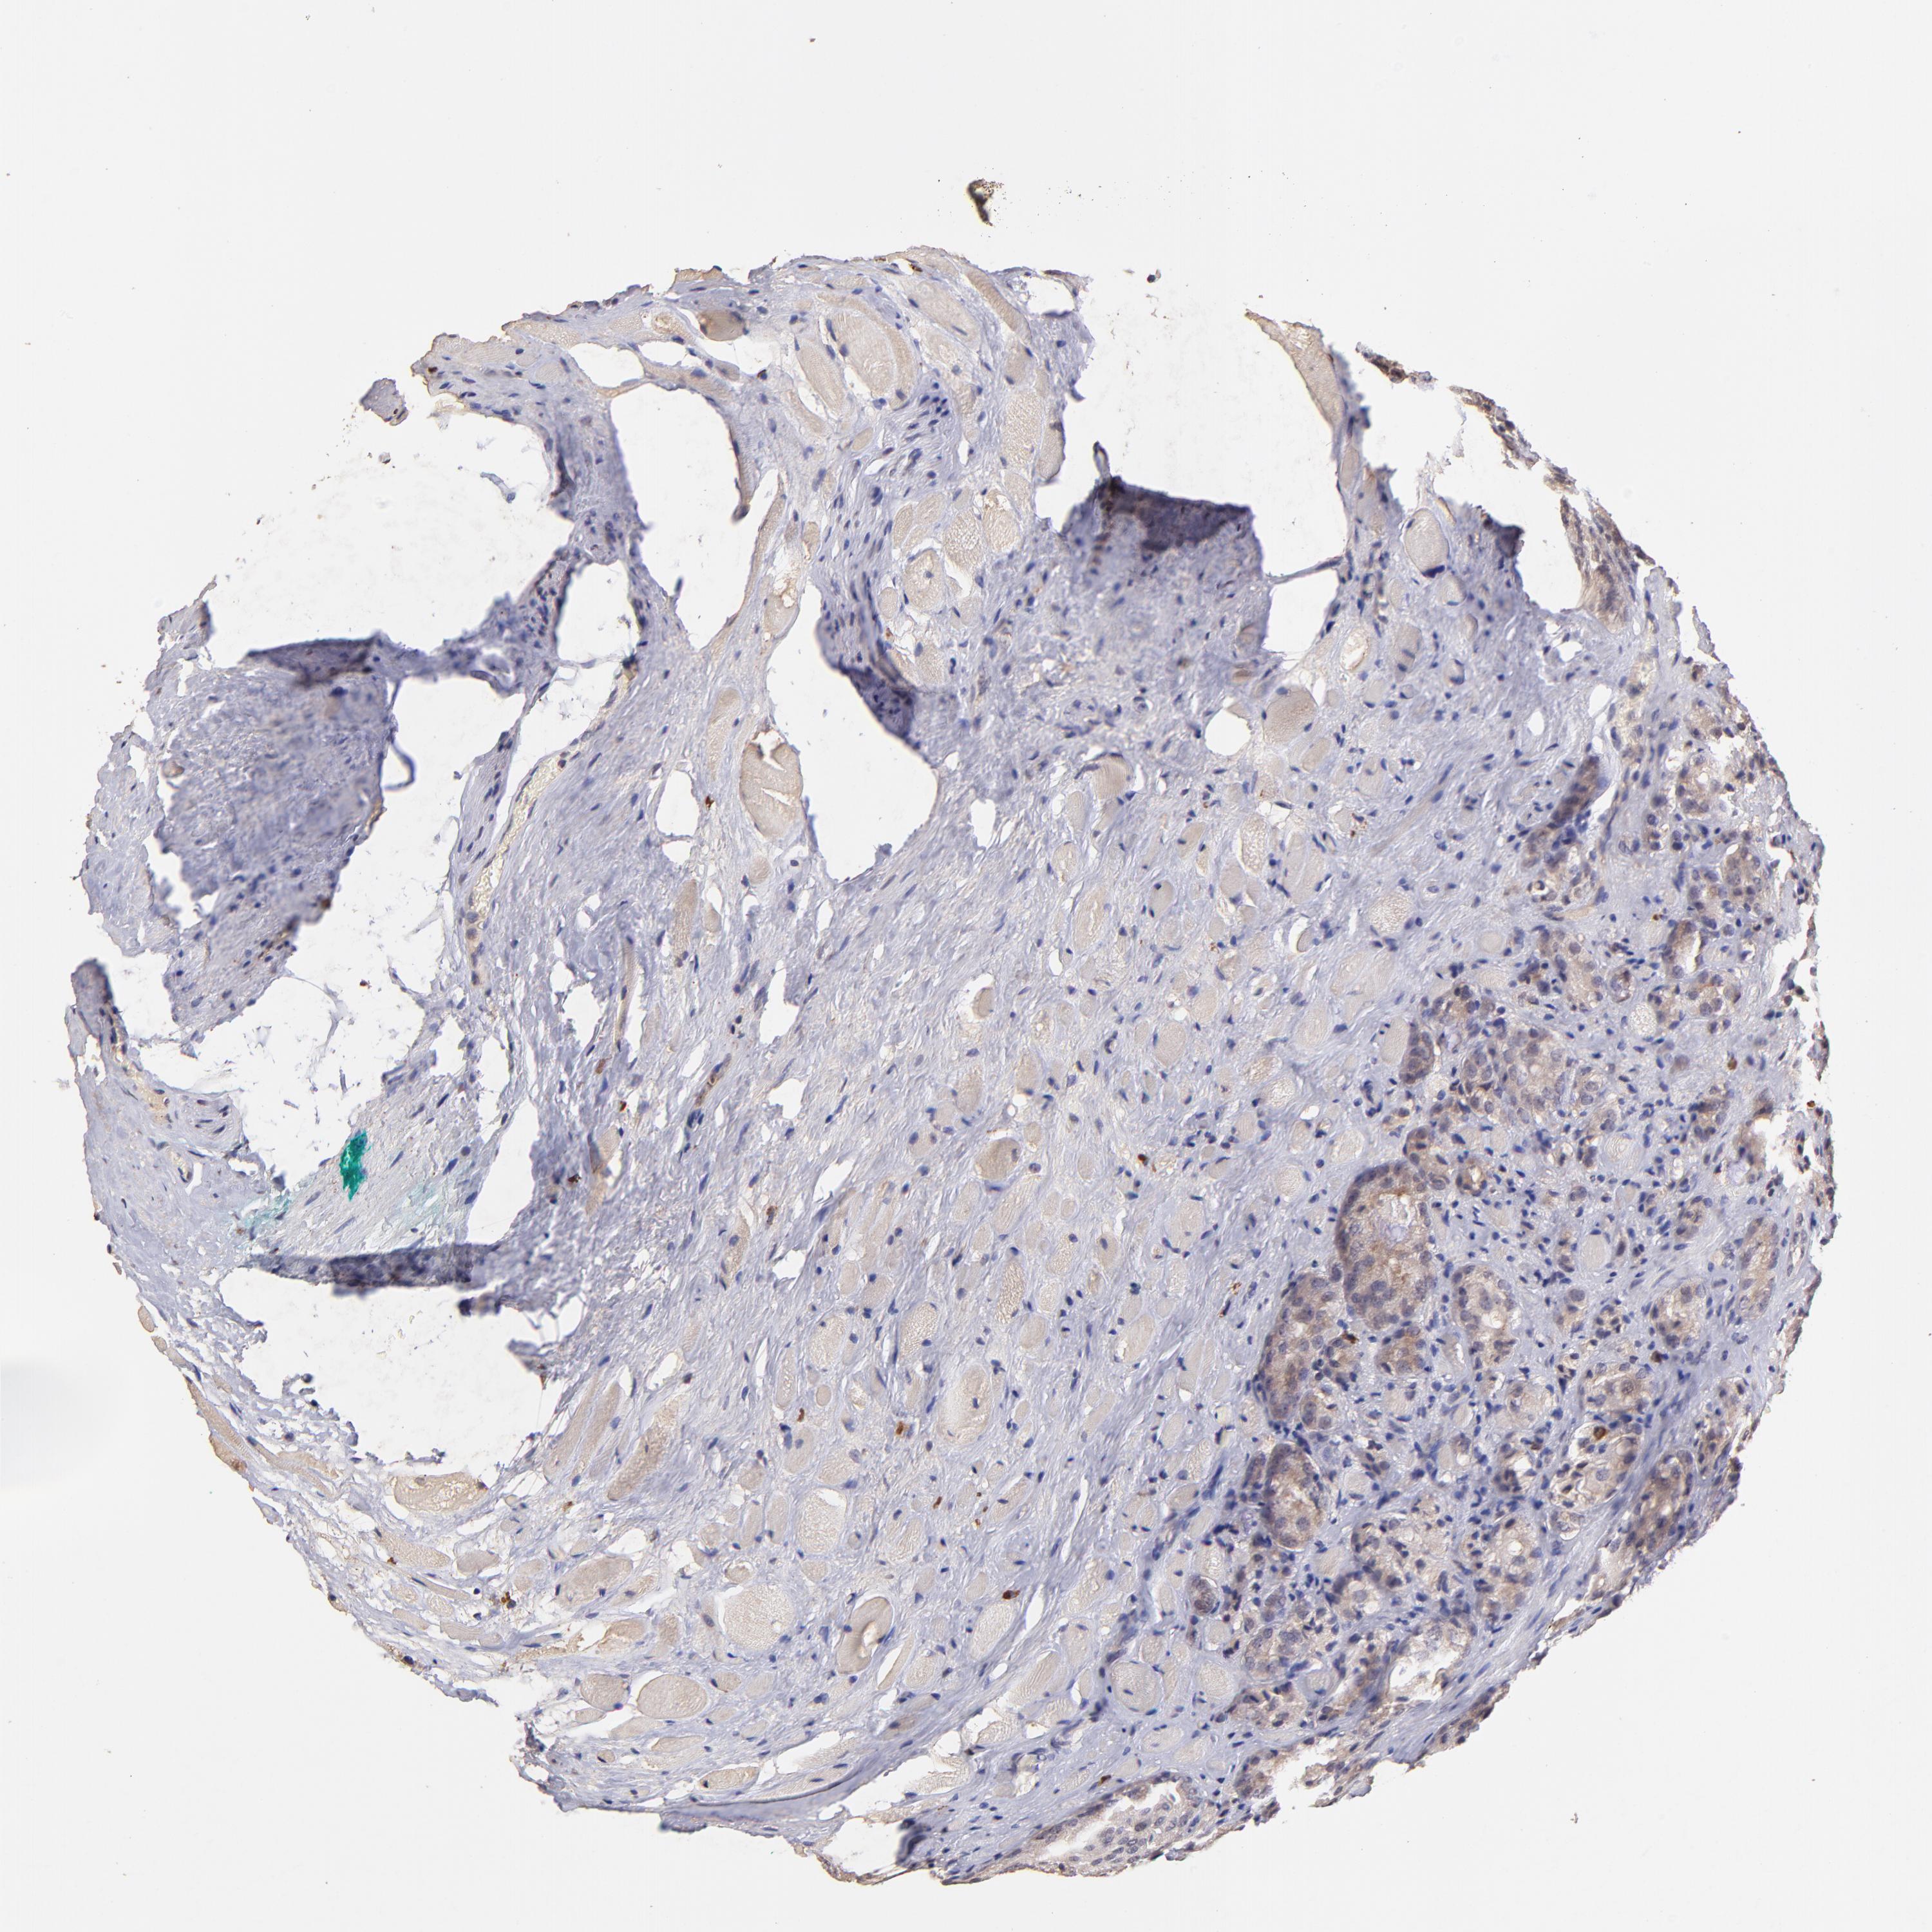

PROSTATE CANCER - Protein expressioni

A mouse-over function shows sample information and annotation data. Click on an image to view it in a full screen mode. Samples can be filtered based on level of antibody staining by selecting one or several of the following categories: high, medium, low and not detected. The assay and annotation is described here.

Antibody stainingi

Antibody staining in the annotated cell types in the current human tissue is reported as not detected, low, medium, or high, based on conventional immunohistochemistry profiling in selected tissues. This score is based on the combination of the staining intensity and fraction of stained cells.

Each image is clickable and will lead to virtual microscopy that enables deeper exploration of all samples and also displays staining intensity scores, fraction scores and subcellular localization as well as patient and tissue information for each sample.

Antibody HPA002633

Antibody HPA046758

Antibody CAB010906

Staining

High

Medium

Low

Not detected

Intensity

Strong

Moderate

Weak

Negative

Quantity

>75%

75%-25%

<25%

None

Location

Nuclear

Cytoplasmic/membranous

Cytoplasmic/membranous,nuclear

Adenocarcinoma, Medium grade

Adenocarcinoma, High grade

Adenocarcinoma, Low grade

Adenocarcinoma, NOS